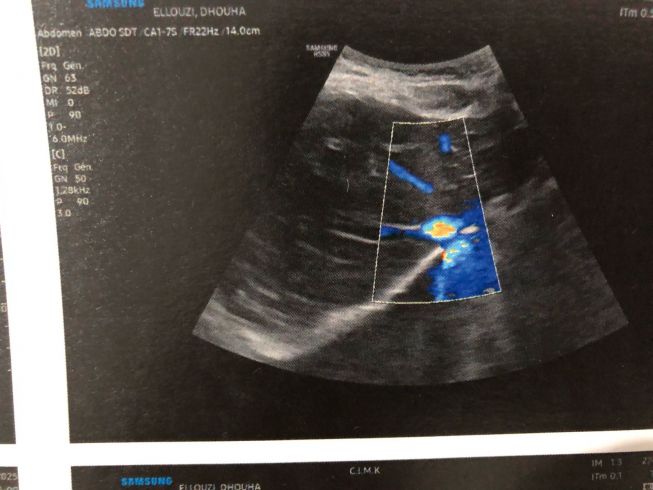

أنا طالبة عمري 21 سنة، أُعاني منذ فترة من حصاة في الحالب حجمها حوالي 6 ملم، مسببة لي آلامًا شديدة وتسببت حسب نتيجة السكانير في توسّع كبير في مجاري البول والكلية.

الطبيب أكّد أن وضعي يحتاج إلى وحتى كيف استعملت الدواء ماحبتش تتداوى تحاليل وأدوية عاجلة، وبنسبة كبيرة تدخّل جراحي لتفادي أي مضاعفات خطيرة لا قدّر الله.